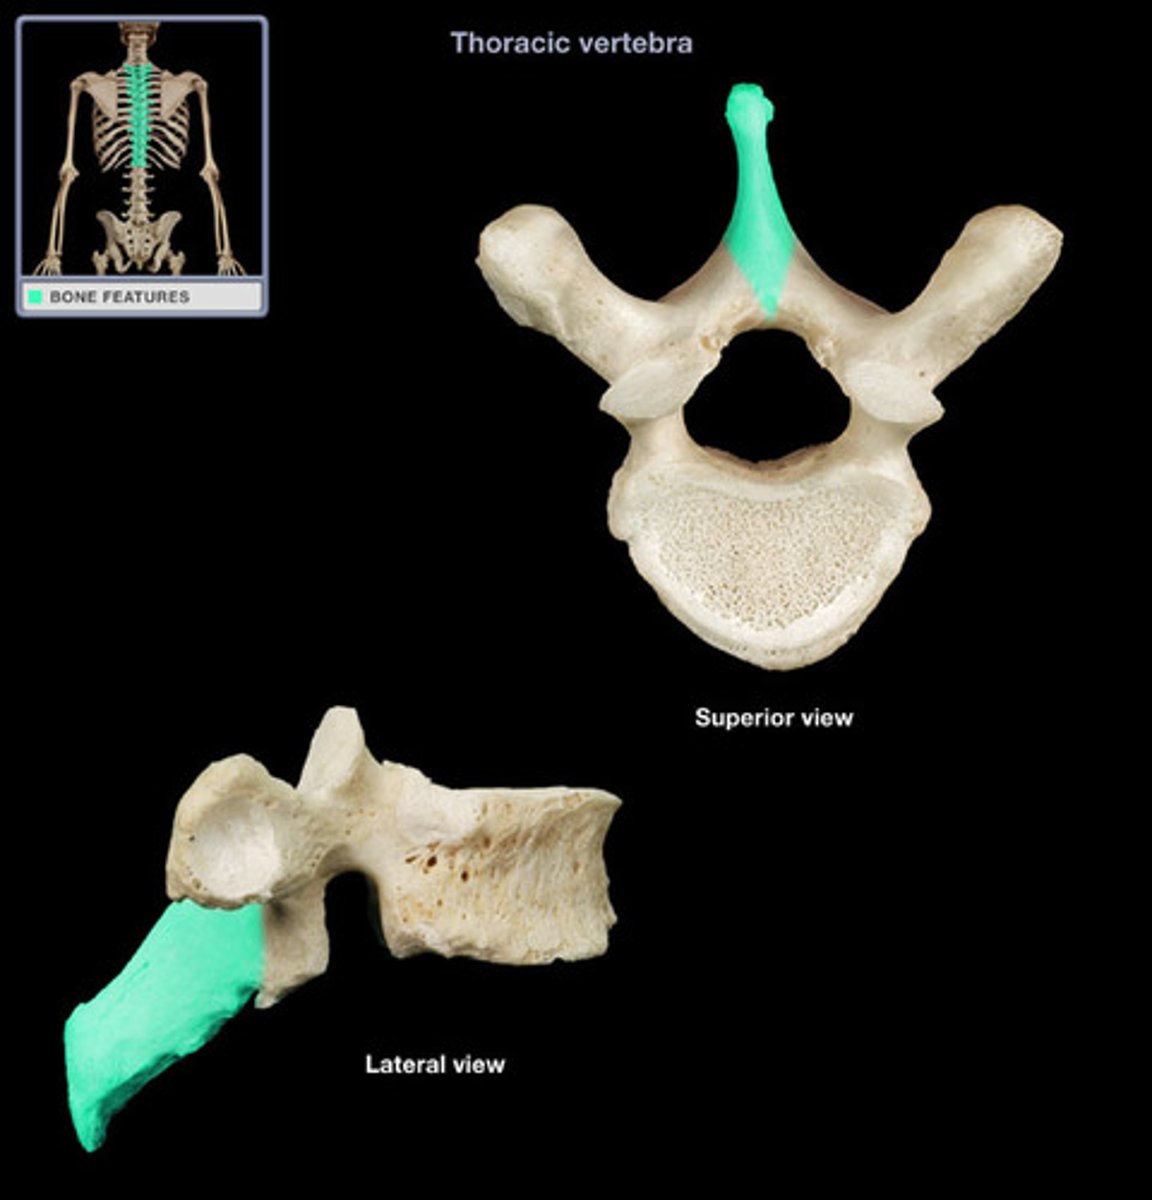

spinous process

bifid spinous process

C2-C6

what sections contain the bifid spinous process

C7

which cervical vertabra has no bifid process (not seperated into two little horns)

what level is the vertebra prominens located

what differenciates the T spine vertebra